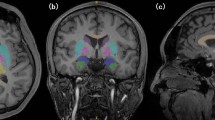

Each set of 3D MPRAGE images was converted from digital imaging and communication in medicine (DICOM) into Neuroimaging Informatics Technology Institute (NIFTI) format and uploaded onto the pipeline volBrain (https://volbrain.upv.es) [22]. It is based on the following preprocessing steps: denoising using the spatially adaptive non-local-means (SANLM) filter [23], coarse inhomogeneity correction [24], registration to Montreal Neurological Institute (MNI) space [25], fine inhomogeneity correction using statistical parametric mapping (SPM) [26], intensity normalization [27]. After that, further steps follow to aid the estimation of brain volumes at different scales: non-local intracranial cavity extraction (NICE) [28], tissue classification [29], non-local hemisphere segmentation (NABS) [30] and non-local subcortical structure segmentation [31].

For this investigation we measured total intracranial volume (TIV), defined as the sum of intracranial grey matter (GM), white matter (WM) and cerebrospinal fluid (CSF), normalized brain volume (NBV), defined as the sum of GM and WM divided by TIV, as well as deep grey matter volumes of the thalamus, globus pallidus, putamen, caudate nucleus, nucleus accumbens and amygdala, respectively. Volume values for both sides were added.